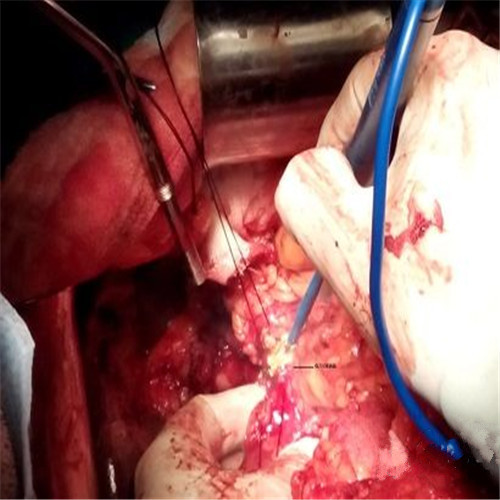

潰瘍性結腸炎微創手術

潰瘍性結腸炎手術中